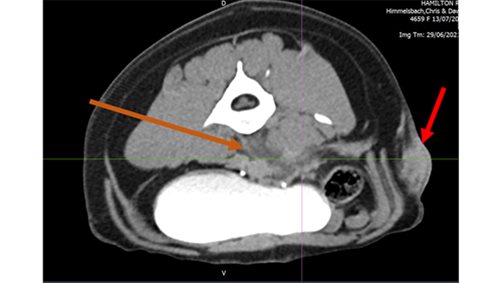

Left image: Orange area – fluid pocket ventral to spinal vertebrae, Red area – subcutaneous mass on left flank

Right image: Mass behind left shoulder